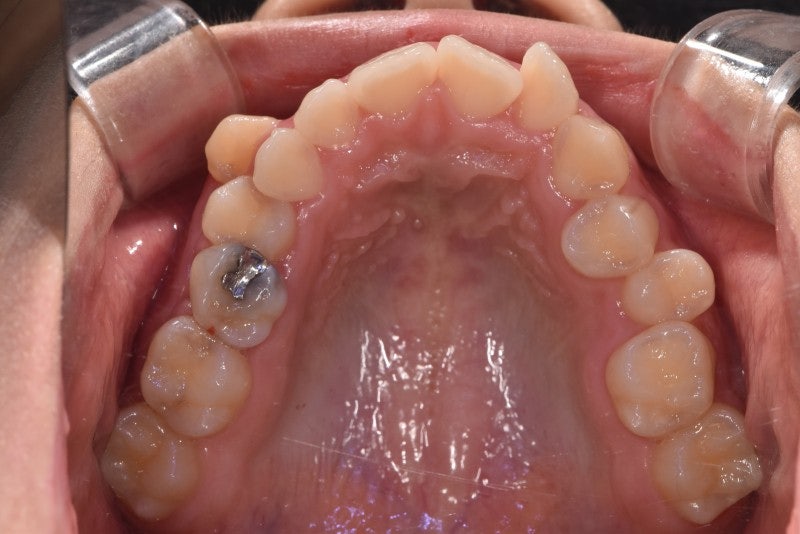

사례 2(양측 대칭 상악 확장)